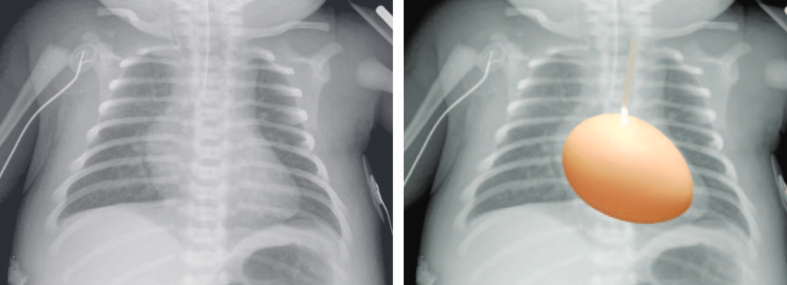

Transposition des Grands Vaisseaux (TGV)

- Malformation cardiaque cyanogène la plus fréquente

- Simple dans 50% des cas

- Malformations Cardiaques autres: CIV (la rend moins détectable)

Signe de l’oeuf sur un fil

- Rétrecissement du médiastin supérieur (ficelle)

- Atrophie du thymus (stress)

- Superposition de l’aorte avec le tronc pulm

- Coeur “globulaire” (oeuf)